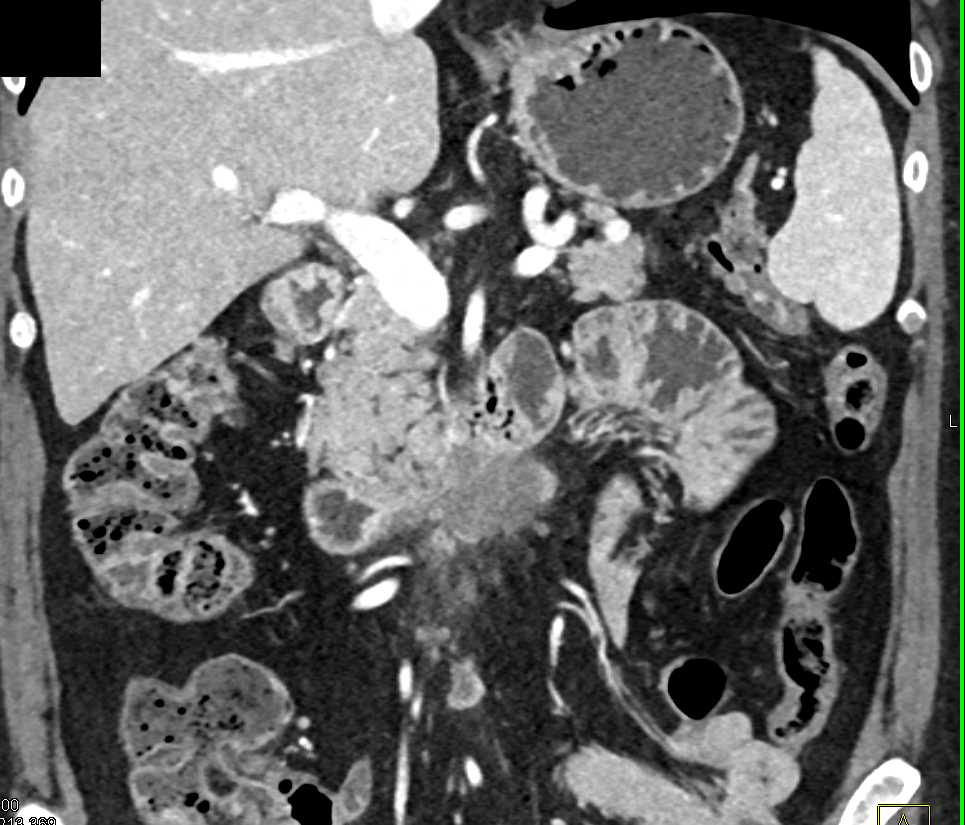

Duodenal Carcinoma with Obstruction